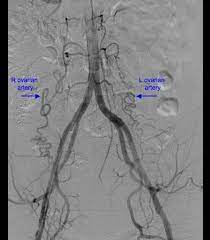

10+ Left Ovarian Artery Anatomy. Gross anatomy origin the ovarian artery arises anterolaterally from the aorta just inferior to the renal arteries and superior to the inferior mesenteric arter. It arises from the abdominal aorta below the renal artery.

Ovary is mainly supplied by ovarian artery which a branch of aorta and arises at the level of l1 vertebra.